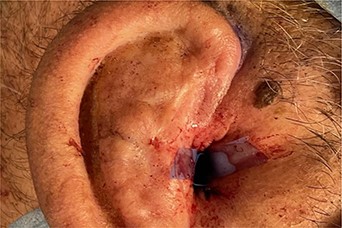

A 56- year old male was presented in the Outpatient Department of Otolaryngology Clinic with main complaint of complete aural atresia of the right ear. The clinical examination revealed that there was no external auditory canal in the right ear (Fig. 1) and hearing loss was altered (Fig. 2). There was no symptomatology in the left ear and the anatomic structures were completely normal. Blood test was normal, and there were no other medical issues from the personal history. The computed tomography (CT) scan and mainly the magnetic resonance imaging (MRI) of the temporal bone revealed no mastoid air cells and no external auditory canal and auricle (Figs 3 and 4). There was a normal anatomy of the internal auditory canal on both sides. Left side of the external auditory canal was normal. Diagnosis of this anatomical malformation was compatible with congenital atresia of the external auditory canal on the right temporal region. The patient decided to proceed to surgery many years after the first diagnosis. Some weeks ago, canalplasty and tympanoplasty were performed by our surgery team. During surgery, a graft has been obtained in order to formate the covering of the new canal. The incision was made behind the ear at the level of temporal bone, and the graft needed is removed from the temporal fascia and inserted as covering of the new canal. The aim is to create a new anatomic pathway resembling a normal external acoustic canal by drilling the atretic bone and removing the present tissue (Figs 5 and 6).

Preoperative examination includes blood tests, audiogram and mostly imagistic examination. CT scan and MRI are necessary for evaluating the surrounding anatomical structures, the deformities and are quite helpful in the surgery plan. In this present case, the imagistic examination revealed unilateral mastoiditis, right atresia of the external acoustic canal and normal anatomy of the other unaffected side. According to Jahrsdoerfer grading system [4], the surgical success can be based on some clinical features regarding the profile of candidates for operation. Based on CT scan and identifying the anatomical structure, such as oval window open, middle ear space, facial nerve, malleus incus complex, mastoid pneumatization, incus-stapes connection, round window and external ear, a score is calculated, and if it is >7/10, surgical success is predicted [5, 6]. The treatment of this anatomical malformation is only surgical repair, resulting in the formation of a new bony canal resembling the external auditory one, by drilling the atretic bone and widening the closed space by removing the stenotic tissue [7]. Repair of the stenotic canal can be succeeded by anterior or posterior approach. In our case, anterior approach has been chosen. The mastoid antrum approach as and operative technique is quite reliable [8]. Removal of the stenotic and fibrotic abnormal tissue requires drilling of the atretic plate over the temporal line behind the glenoid fossa. The drilling stops at the borders of the anterior epitympanium. When the new canal is formatted, it is covered by graft. The goal is to maintain the width of new aural canal. The reconstructed auricle requires use of porous polyethylene material (MedPor) or autologous rib cartilage [8, 9]. In our patient, the auricle was repaired some years ago before the surgical repair of the atretic external auditory canal.

If left untreated, this anatomical malformation may lead to language and learning skills problems to the patient. Due to the abnormal acoustic pathway, there is also an increased risk of benign tumor formation, such as cholesteatoma, which will need surgical repair in the future. Post-operatively, there has to be a follow-up of the new graft and canal. One of the most common complications can be displacement of the new tympanic membrane and restenosis [10].